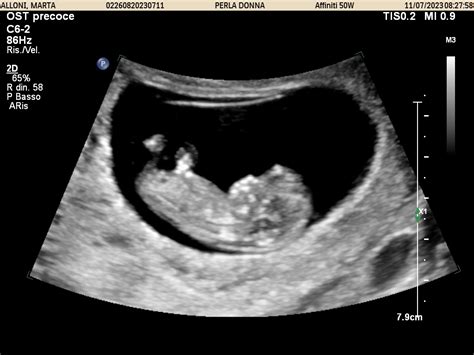

La diagnosi prenatale, attraverso varie tecniche, permette di identificare molte anomalie congenite durante lo sviluppo fetale. La misurazione della translucenza nucale tra l'11a e la 13a settimana gestazionale, combinata con marcatori biochimici, consente di valutare il rischio di alcune cromosomopatie. Sebbene la fisiopatologia dell'aumento della translucenza nucale non sia completamente chiara, una compromissione dell'attività cardiaca, la congestione venosa, un'alterata matrice extracellulare, o problemi al sistema linfatico sono tra le cause ipotizzate.

Nel secondo trimestre, l'ecografia morfologica permette uno studio accurato dell'anatomia fetale, identificando malformazioni comuni come cardiopatie, anomalie cerebrali, intestinali e renali. La diagnosi prenatale non invasiva (NIPT), eseguita su sangue materno a partire dalla decima settimana, analizza il rischio delle trisomie più comuni (21, 18, 13) e delle aneuploidie dei cromosomi sessuali con elevata attendibilità.

La diagnosi delle anomalie congenite si avvale di diverse tecniche. L'ecografia, in particolare quella del secondo trimestre (morfologica), è fondamentale per lo studio dell'anatomia fetale. Test di screening non invasivi su sangue materno (come il test Harmony) valutano il rischio di anomalie cromosomiche. Test invasivi come l'amniocentesi e la villocentesi forniscono una diagnosi definitiva delle anomalie genetiche e cromosomiche.